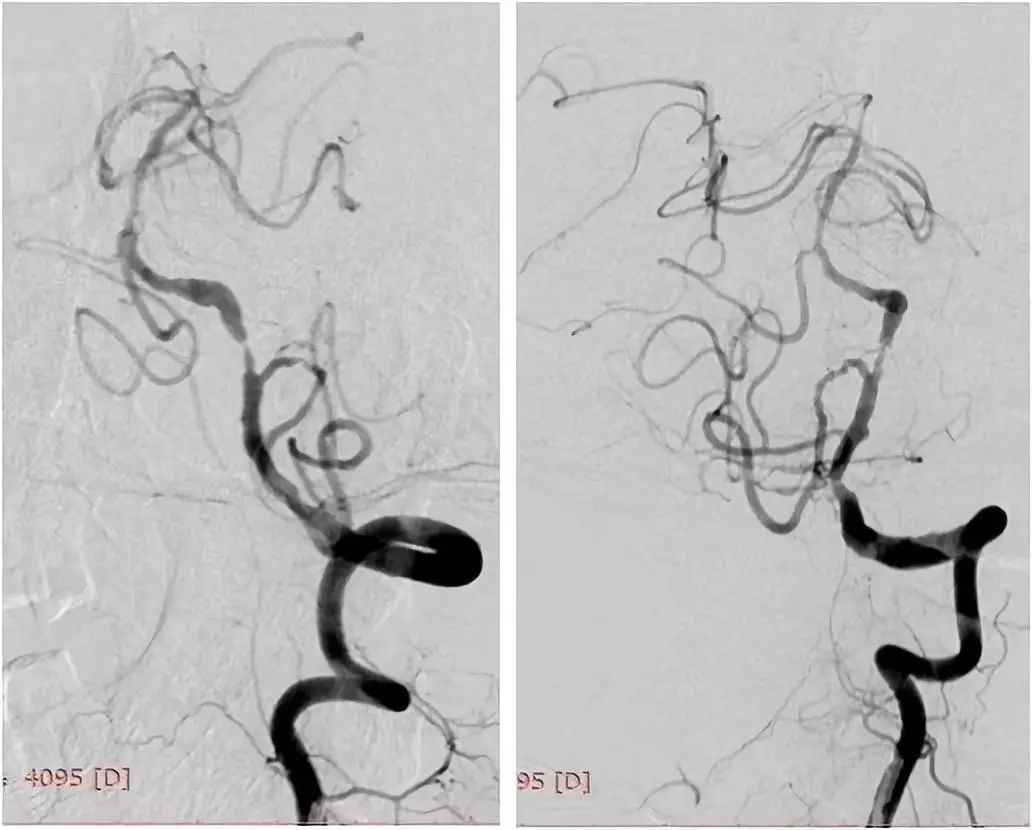

DSA:右颈内动脉C6段重度狭窄;双侧胚胎型大脑后动脉;左椎动脉V1段迂曲,V4段重度狭窄;右椎动脉纤细,V4段以远显影欠佳(图3-6)。

图3

图4

图5

图6